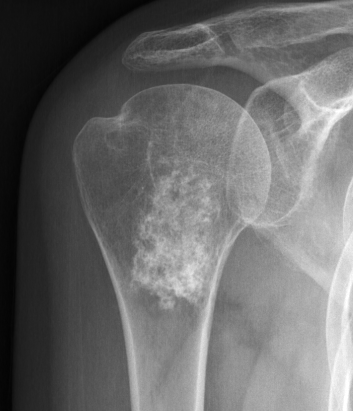

X-ray

Intralesional calcification - punctate, stippled calcification and broken rings

Enchondroma versus chondrosarcoma

Murphey et al Radiographics 1998

- 92 enchondromas versus 95 chondrosarcomas

- factors associated with chondrosarcoma on presentation and imaging

- pain

- deep endosteal scalloping (>2/3 cortical thickness)

- cortical destruction

- soft tissue mass

- high uptake on bone scan